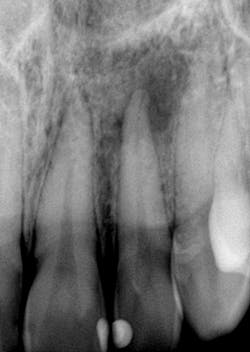

I recently had a young lady come in with multiple teeth darkened from trauma that happened years ago. It was for a consult to consider endo/internal bleaching.So, which do you think?

- Endodontic treatment of no. 9, 10, and 11 (with conservative accesses) with internal bleaching and lingual restorations posttreatment? Or…

- Treat no. 10 and then do full porcelain coverage on all incisors since the shading is light enough for coverage and no show-through.